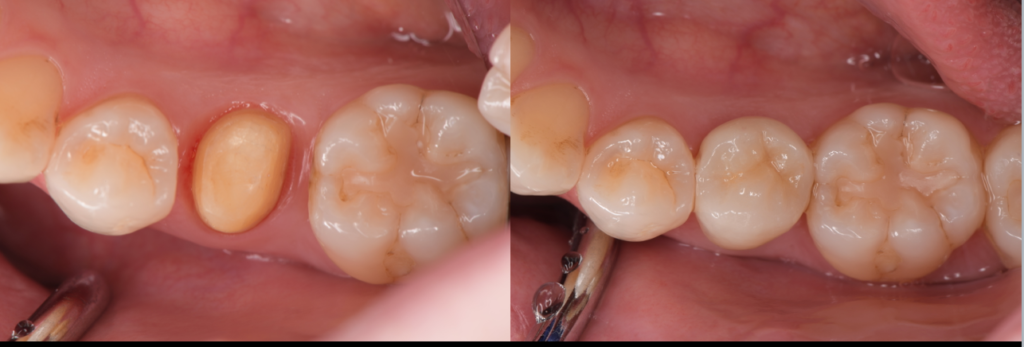

ダイレクトボンディングによる虫歯治療のメリット

「できるだけ歯を削らず、きれいに、長持ちする虫歯治療を受けたい」そんな方に今、選ばれているのがダイレクトボンディングです。

そしてこの治療は、どこで受けるかによって結果が大きく変わる治療でもあります。

奥歯をセラミックで治すメリットとは?

1. 奥歯でもしっかり噛める高い強度

「セラミックは割れやすいのでは?」という不安を持つ方もいますが、現在の歯科用セラミックは技術の進歩により非常に高い強度を持っています。特に奥歯には、ジルコニアなど噛む力に強いセラ…